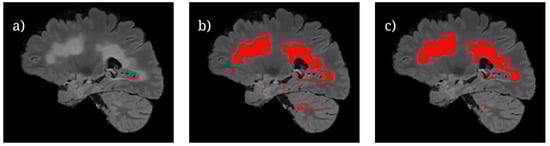

Testing had been performed using nine patients of the combined dataset for each fold. In each fold, six of the patients had been from the UMCL dataset, and three of the patients had been from MSSEG 2016 dataset; this was conducted in order to keep the training and testing ratio consistent between both datasets. The final testing metrics are averages of each validation fold. Additionally, the testing predictions of the best model-input combination were visualized as contours over the corresponding MRI in order to qualitatively evaluate the model’s segmentation performance.

Figure 6 shows the U-Net++ CEN predictions of lesion locations during testing. It is important to note that while larger volumes of lesions are able to be segmented proficiently by the model, there are still differences between the predictions and ground truth for smaller lesion fragments. This is most likely due to the difficulty in classifying small lesion volumes in isolation. A potential avenue of investigation with regards to this observation is to train the model by using specific regions of a brain slice where the lesions are known to be smaller. This is similar to an attention-based model framework which has been known to perform well [13], but it would require significantly more labeled data.

Figure 6. Segmentation results for U-Net++ with ResNeXt-50 when using FLAIR: (a) sagittal FLAIR slice, (b) overlayed ground truth lesions (red), and (c) overlayed model predictions (red).